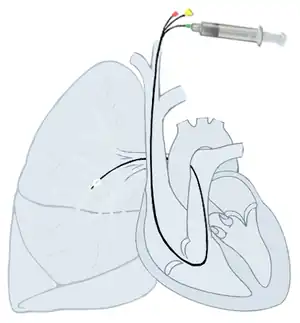

Right heart catheterization (RHC) allows the physician to determine the pressures within the heart (intracardiac pressures). The heart is most often accessed via the internal jugular or femoral vein; arteries are not used. Values are commonly obtained for the right atrium, right ventricle, pulmonary artery, and pulmonary capillary "wedge" pressures. Right heart catheterizations also allow the physician to estimate the cardiac output, the amount of blood that flows from the heart each minute, and the cardiac index, a hemodynamic parameter that relates the cardiac output to a patient's body size. Determination of cardiac output can be done by releasing a small amount of saline solution (either chilled or at room temperature) in one area of the heart and measuring the change in blood temperature over time in another area of the heart.

Right heart catheterization is often done for pulmonary hypertension, heart failure, and cardiogenic shock. The pulmonary artery catheter can be placed, used, and removed, or it can be placed and left in place for continuous monitoring. The latter can be done an intensive care unit (ICU) to permit frequent measurement of the hemodynamic parameters in response to interventions.